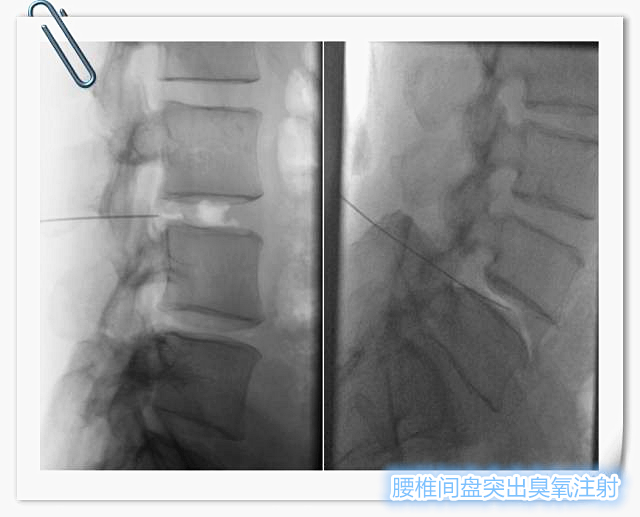

腰椎间盘臭氧注射术

腰椎间盘臭氧注射术 已是国内外临床成熟于治疗腰椎间盘突出症的微创方法。主要原理是将臭氧注射人椎间盘内,破坏髓核中的蛋白多糖,使髓核变性、坏死、萎缩,从而缓解对神经根的压迫。同时臭氧尚有止痛、消除神经根无菌性炎症、减轻免疫反应等优点。椎旁注射臭氧能够缓解腰大肌痉挛及减少脂肪化,对于维持脊柱的稳定性有重要意义。在各种治疗椎间盘突出的方法中,臭氧治疗是创伤小、并发症少、安全有效的治疗方式。

在DSA实时引导下,精确穿刺病变椎间盘,注射臭氧进行病变椎间盘髓核消融治疗,后退针至椎旁策划注射臭氧及消炎镇痛剂。